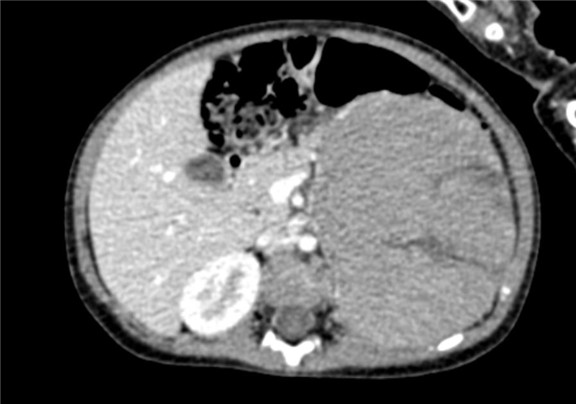

术前CT检查:

静脉期

2017-02-03 上腹部CT平扫:左肾区巨大占位,肾母细胞瘤?建议CT增强检查;右肾结石可能性大;腹腔积液。